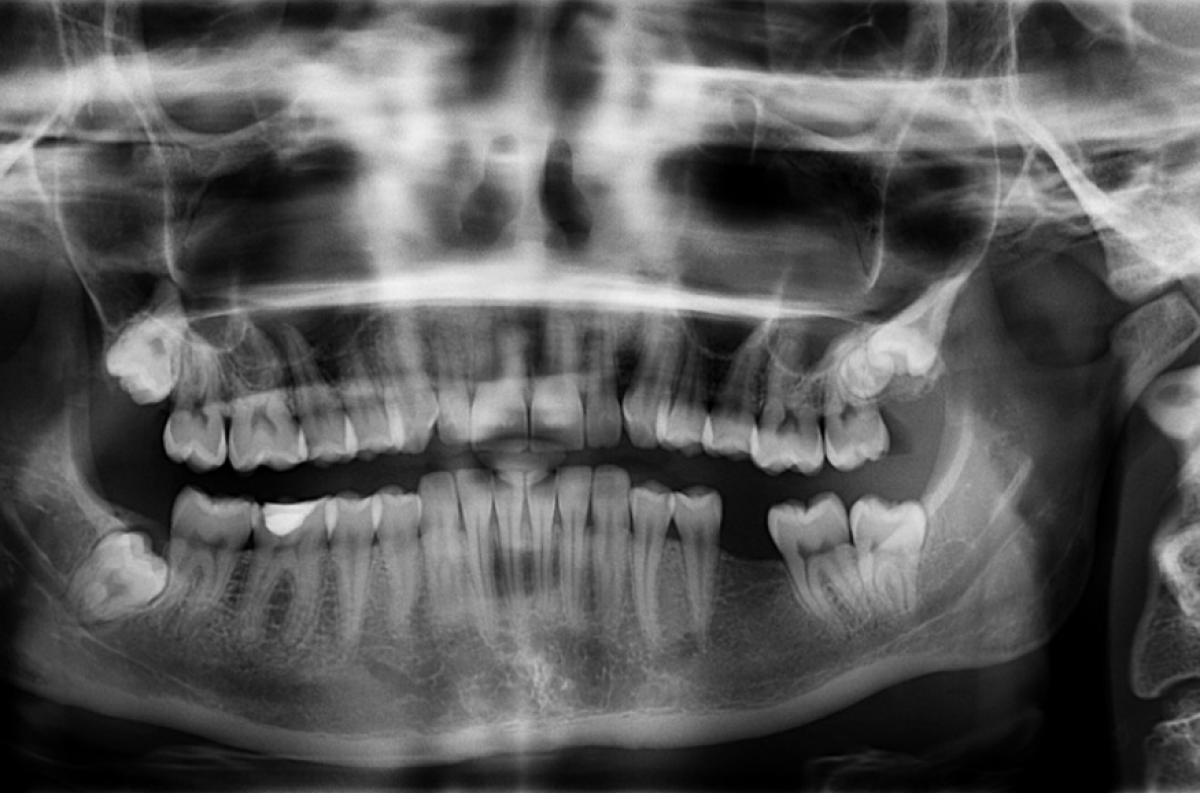

“Нужно было сделать снимок, и врачи спросили, что это за предмет. По форме я сразу поняла, что это та самая пуля из тира”.

Обследование показало, что пуля прошла через губу, через зубы, через щеку и застряла в жевательной мышце.

“В больнице мне объяснили, что пулю можно удалить или оставить, так как за это время она закапсулировалась”, – отметила девушка.